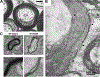

Excessive alcohol use has adverse effects on the central nervous system (CNS) and can lead to alcohol use disorders (AUDs). Recent studies have suggested that myelin reductions may directly contribute to CNS dysfunctions associated with AUDs. Myelin consists of compact lipid membranes wrapped around axons to provide electrical insulation and trophic support. Regulation of myelin is considered as a new form of neural plasticity due to its profound impacts on the computation of neural networks. In this review, the authors first discuss experimental evidence showing how alcohol exposure causes demyelination in different brain regions, often accompanied by deficits in cognition and emotion. Next, they discuss postulated molecular and cellular mechanisms underlying alcohol's impact on myelin. It is clear that more extensive investigations are needed in this important but underexplored research field in order to gain a better understanding of the myelin-behavior relationship and to develop new treatment strategies for AUDs.